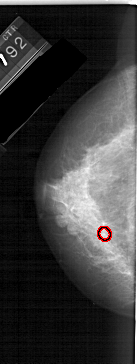

A_1929_1.LEFT_MLO

LEFT_MLO LINES 5236 PIXELS_PER_LINE 2071 BITS_PER_PIXEL 12 RESOLUTION 43.5 OVERLAY

FILE: A_1929_1.LEFT_MLO.OVERLAY

TOTAL_ABNORMALITIES 1

ABNORMALITY 1

LESION_TYPE CALCIFICATION TYPE AMORPHOUS DISTRIBUTION CLUSTERED

ASSESSMENT 4

SUBTLETY 2

PATHOLOGY MALIGNANT

TOTAL_OUTLINES 1

BOUNDARY